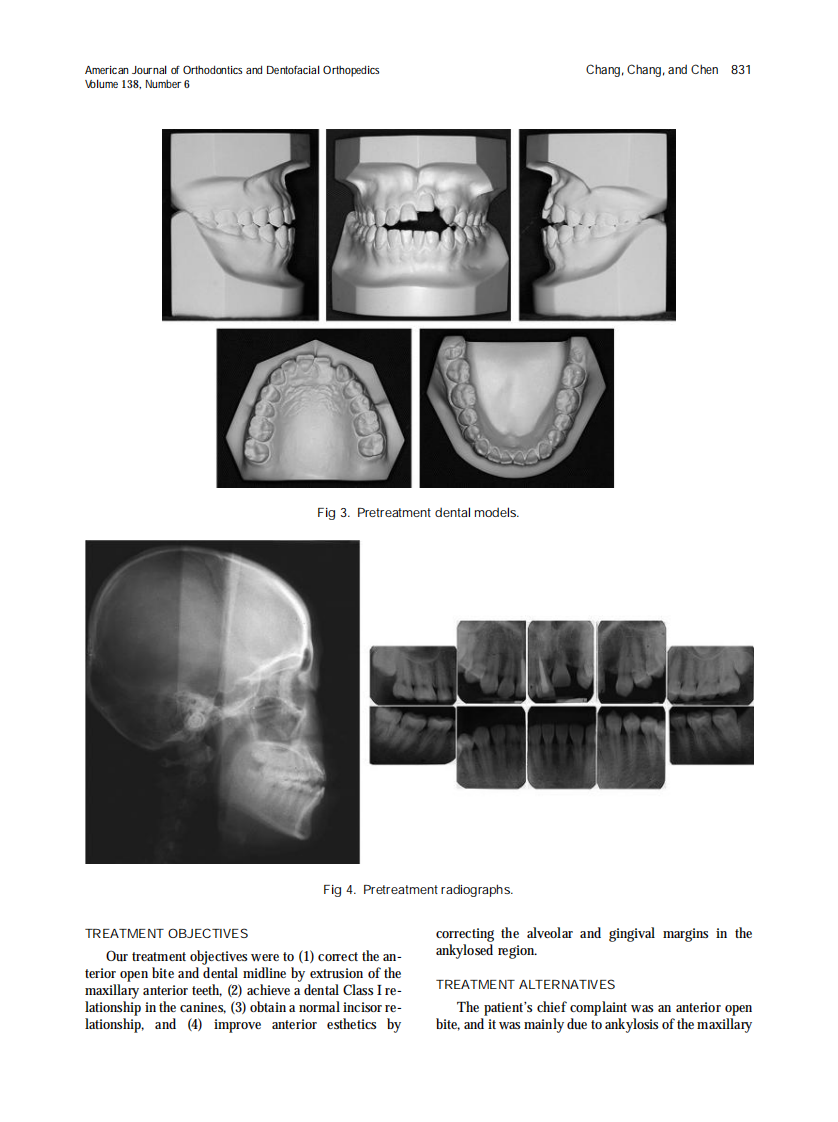

AJO-DO

2010_138_6_829_838.pdf